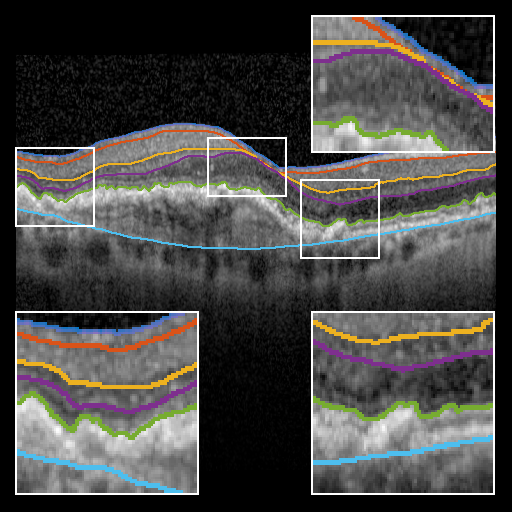

To evaluate BRU-net, we compare it with the 3D methods of Dufour [5], Chen et. al. [4], and the 2D method of Mayer et. al. [12] on the same dataset. Additionally, we train a traditional U-net configuration [14] using the procedure described above. Fig. 3 provides a qualitative comparison of the results.